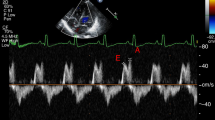

ABSTRACT.: Leukotrienes may control fetal pulmonary vascular tone since infusions of putative leukotriene receptor antagonists markedly increase pulmonary blood flow and decrease pulmonary vascular resistance in fetal lambs. This hypothesis would be strengthened if inhibition of leukotriene synthesis also produced similar hemodynamic changes. We therefore studied the effects of piriprost (U 60257), a putative leukotriene synthesis inhibitor, on thirteen fetal lambs at 137 to 140 days gestation. In preliminary studies in four fetal lambs, doses of U 60257 greater than 20 mg/kg increased pulmonary blood flow. In the nine other fetal lambs, U 60257 (31.7 ± 4.1 mg/kg) increased pulmonary blood flow by 502% (p < 0.05) and decreased pulmonary vascular resistance by 87% (p < 0.05). Pulmonary arterial and left atrial pressures were unchanged. Descending aortic pressure was increased (p < 0.05) and heart rate was decreased (p < 0.05). The abilities of both putative leukotriene synthesis inhibitors and leukotriene receptor antagonists to similarly increase fetal pulmonaryblood flow and decrease pulmonary vascular resistance are consistent with the hypothesis that leukotrienes play a role in regulating fetal pulmonary vascular tone.